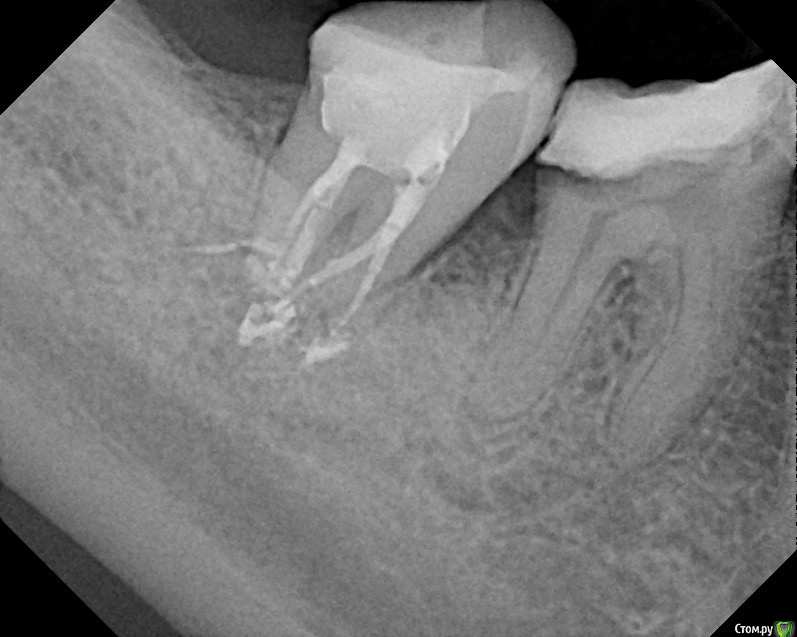

St616 Опубликовано 2 декабря, 2014 Поделиться Опубликовано 2 декабря, 2014 Добрый день ! Прошу вас посмотрите пломбировку каналов метапексомПосле пломбировки 2 дня сильная боль при нажатии и вообще.Сегодня пятый день, зуб поднывает и еще качается.Дело в том что у меня грудной ребенок, я его кормлю и поэтому не хотелось может более сильных, но не безопасных средств. Нервы удаляли с анастезией без лекарств. Тк был предложен только мышьяк. А у меня ребенок га гв. Пломбировка каналов и окончатильная очистка уже через 7 дней в другой клинике, хотели гуттаперчей. Но тк зуб качался сделали метапексом, врач вроде хоть и молодой но оч грамотный. Меня волнует небольшое темное пятно в одном канале под пломбой, это что воздух там? Не из ха этого ди боль сохраняется, сейчас уже небольшая. Воач по снимку сказал, что всё хорошо, а боль из за того что метапекс вышел за пределы. Фото до и после Ссылка на комментарий

anvladd Опубликовано 2 декабря, 2014 Поделиться Опубликовано 2 декабря, 2014 на счет темного пятна не беспокойтесь,а боль из за того что материал вышел за верхушку,должен рассосаться. Боль совсем не утихает? Ссылка на комментарий